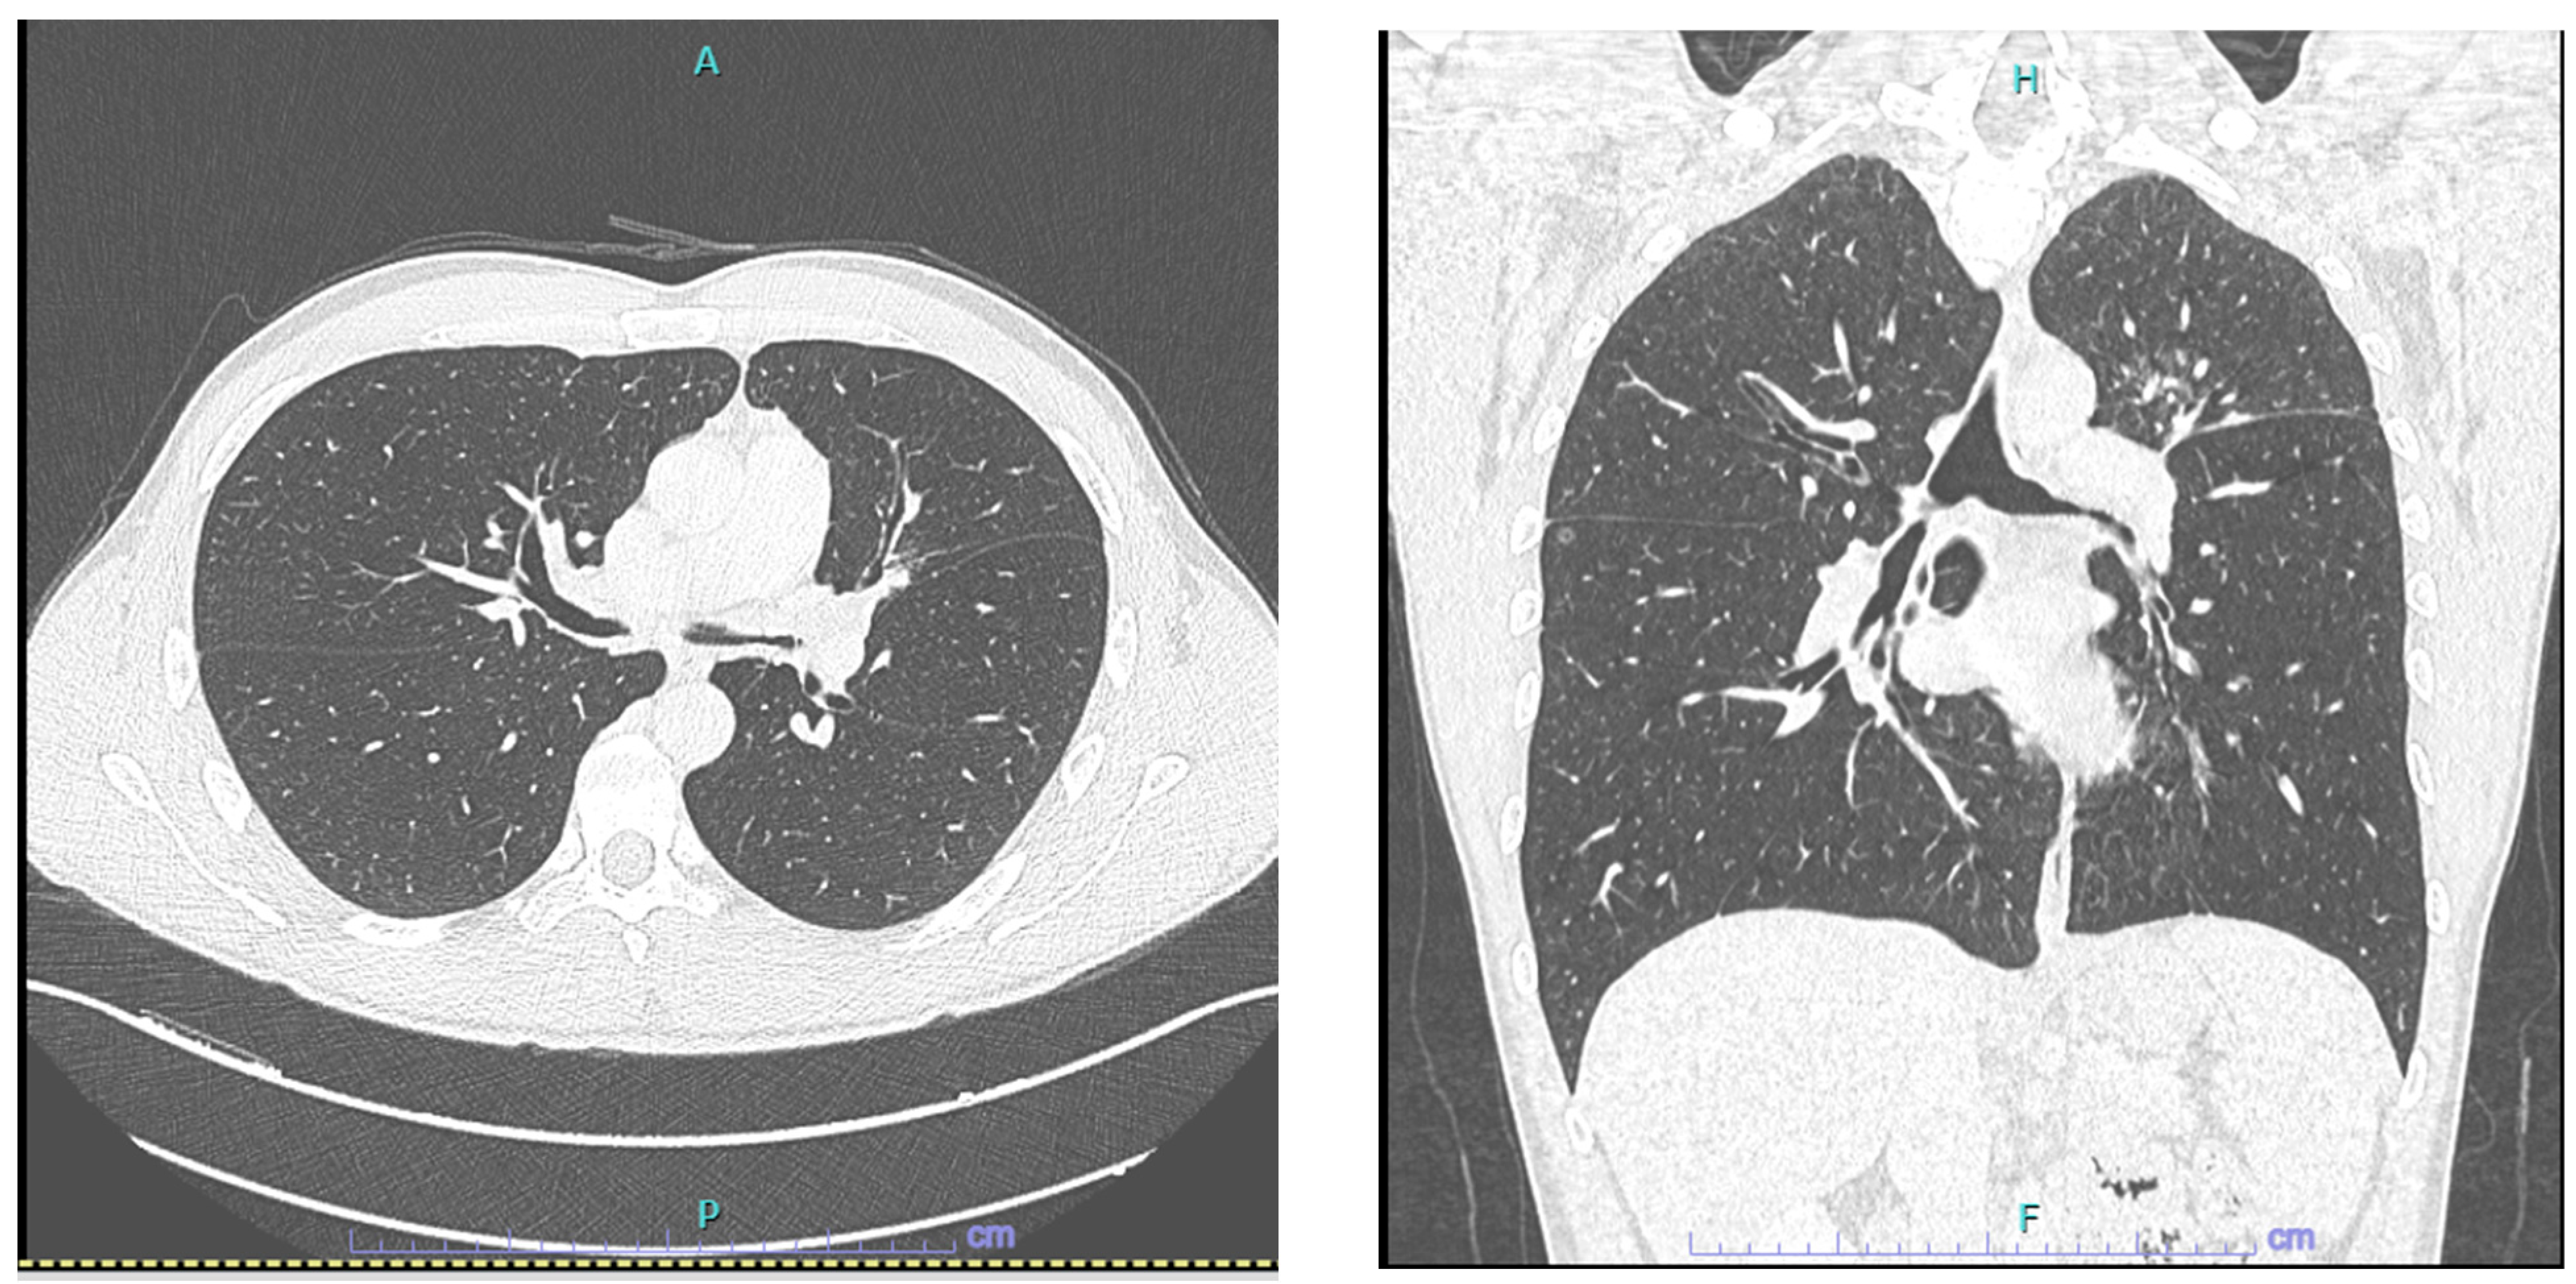

- Pulmonary nodules, mass, or cavitation on chest imaging (+2);